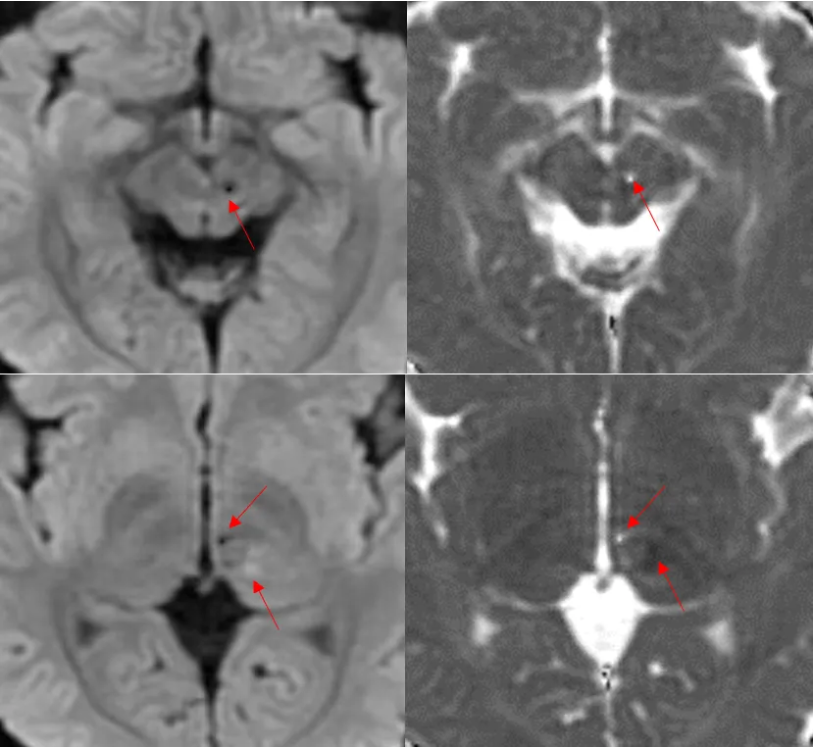

DWI低信号,ADC高信号; DWI稍高信号,ADC略下降。 小朋友,你是否也有很多问号?

要么再试试薄层DWI: MUSE DWI b1000:FOV = 20 , 160(freq)× 512(phase),2 /0mm。 这根狡猾的小静脉终于露出庐山真面目。

常规DWI层厚5 / 1 mm,160 × 192;分辨率已经挺高的了。但是仍旧会存在严重的容积效应。

这个患儿扫描到MP- RAGE的时候,已经陷入深度睡眠(虽然没有吃药)。所以,我们加扫了SWAN和高清MUSE,2mm,矩阵512。为了降低容积效应,我们已经使出了洪荒之力。